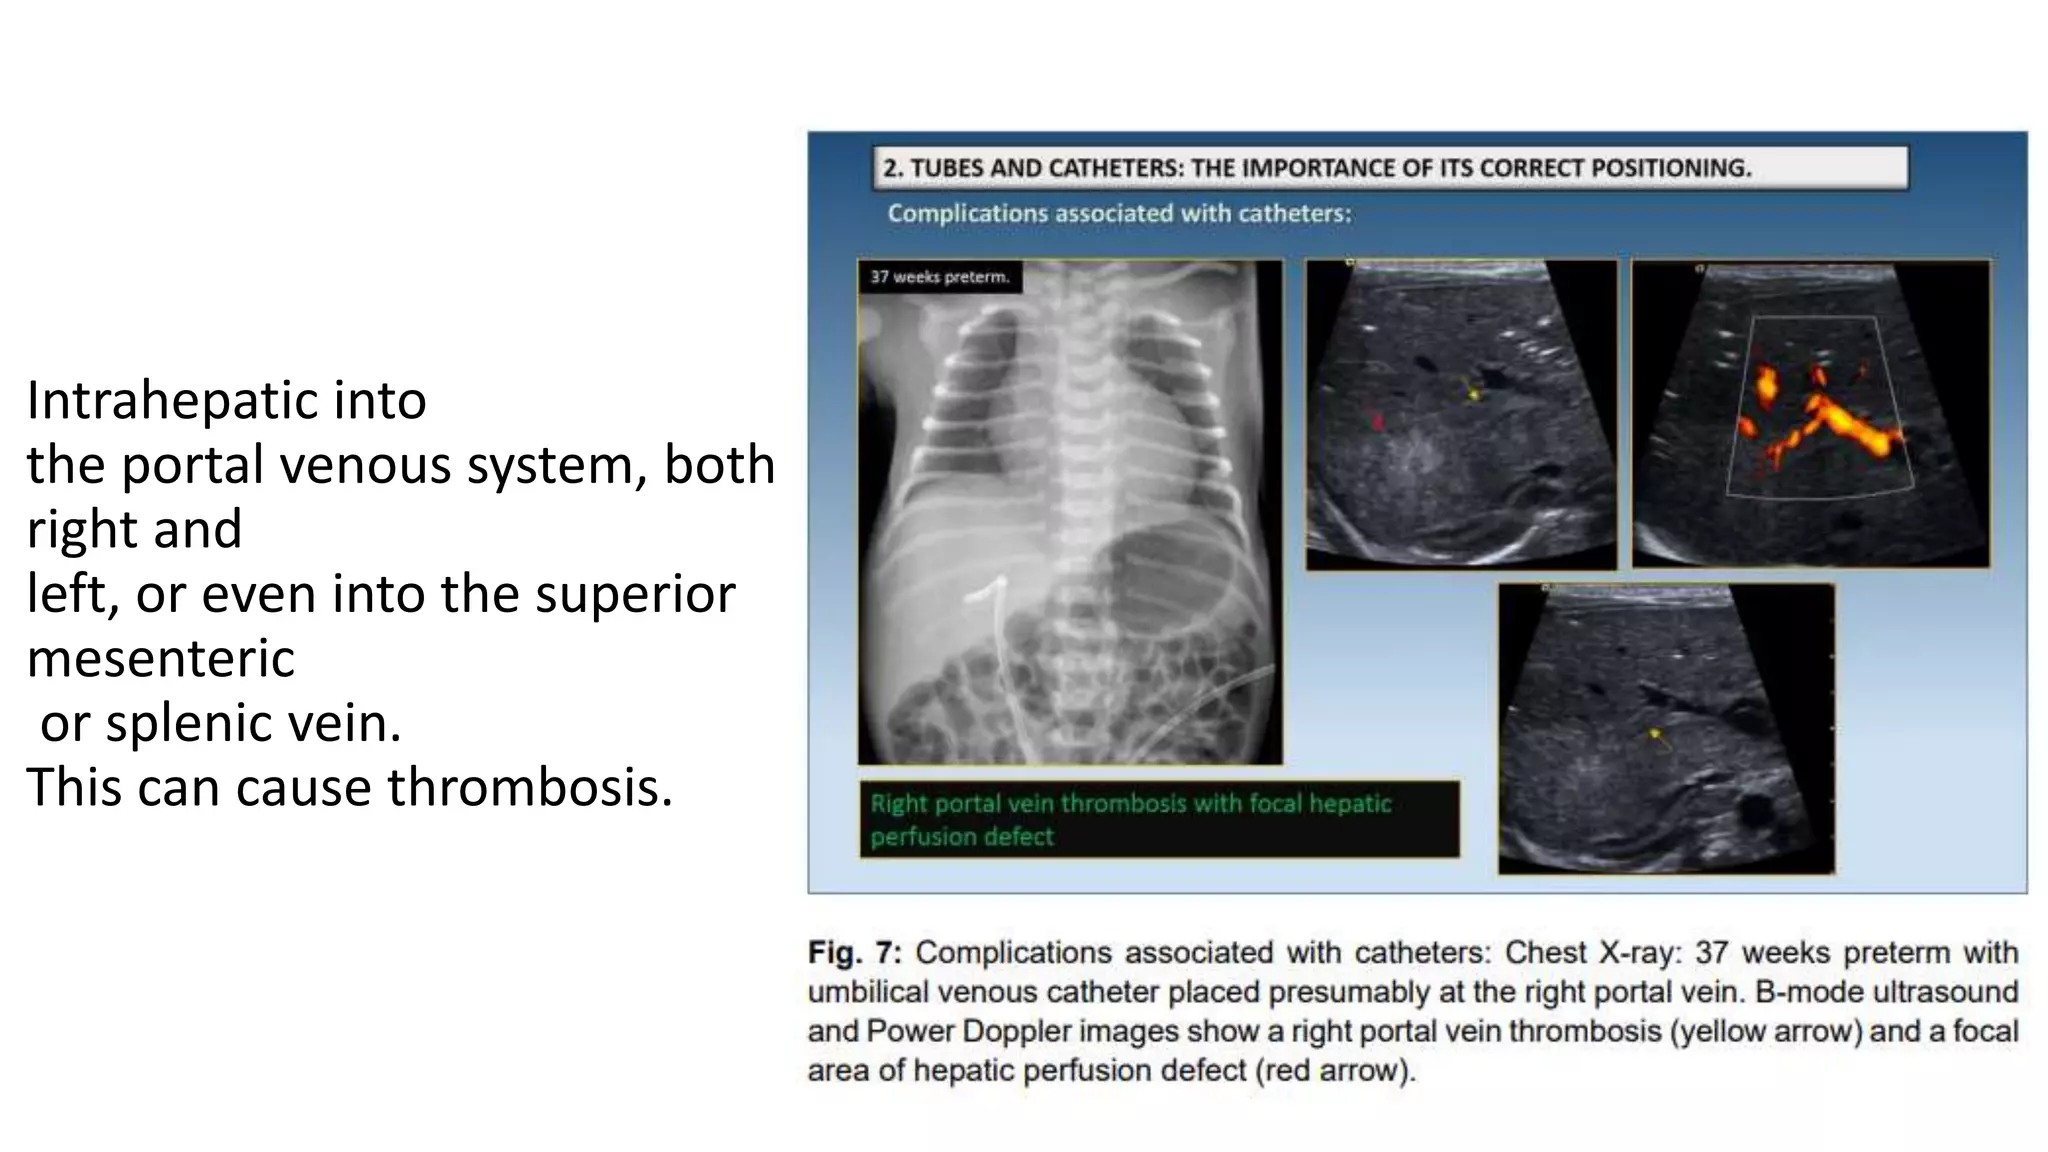

This document provides an overview of neonatal chest x-rays, including when they should and should not be performed, what a normal x-ray looks like, common positions of tubes and catheters, and common causes of respiratory distress in neonates. It discusses the appearance of a normal chest x-ray as well as conditions like respiratory distress syndrome, transient tachypnea of the newborn, meconium aspiration syndrome, and pneumonia. Surgical conditions like diaphragmatic hernia and esophageal atresia are also reviewed.